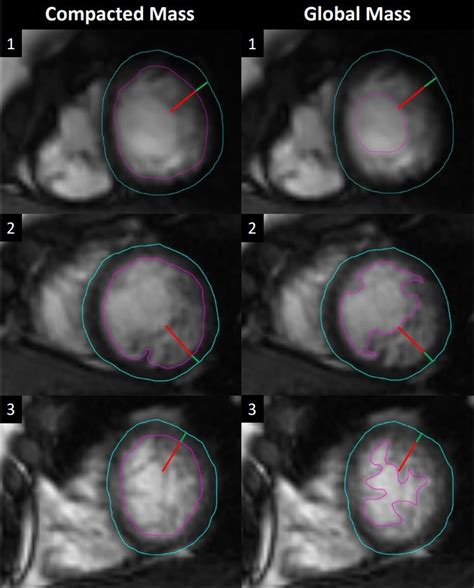

To better understand Non Compaction Cardiomyopathy, it is helpful to visualize the heart's anatomy. Typically, the heart walls are smooth and dense. In patients with NCCM, the myocardium (the heart muscle) remains thin and features excessive trabeculations—small, finger-like projections—and deep inter-trabecular recesses. These structural flaws create a "spongy" appearance when viewed through imaging techniques.

Diagnosing Non Compaction Cardiomyopathy primarily involves advanced cardiac imaging. Physicians utilize specific diagnostic criteria to differentiate NCCM from a normal heart that may just have prominent, yet healthy, trabeculations.

Cardiac MRI Considered the gold standard for accurately measuring myocardial thickness.